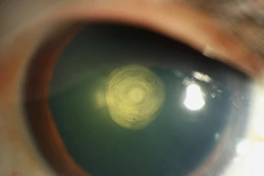

Katarak Posterior Lenticonus/Lentiglobus

Lenticonus/lentiglobus posterior disebabkan oleh penipisan kapsul posterior pusat. Penipisan ini awalnya menunjukkan gambaran butiran menyerupai “tetesan minyak” pada saat pemeriksaan refleks fundus. Seiring dengan berkembangnya kantung lensa, serat kortikal meregang dan secara bertahap menjadi keruh. Proses ini bisa memakan waktu bertahun-tahun. Tetapi jika kapsul ini robek, kekeruhan total lensa dapat terjadi secara cepat. Kekeruhan lentikonus posterior hampir selalu terjadi secara unilateral, dan ukuran mata yang abnormal sama dengan ukuran mata yang normal. Kekeruhan pada Lenticonus/lentiglobus posterior ini biasanya tidak diwariskan, meskipun kelemahan pada kapsul posterior bisa menjadi faktor sifat bawaan. Katarak pada Lenticonus/lentiglobus posterior biasanya tidak terbentuk di masa awal kehidupan sehingga menyerupai karakter katarak yang didapat.